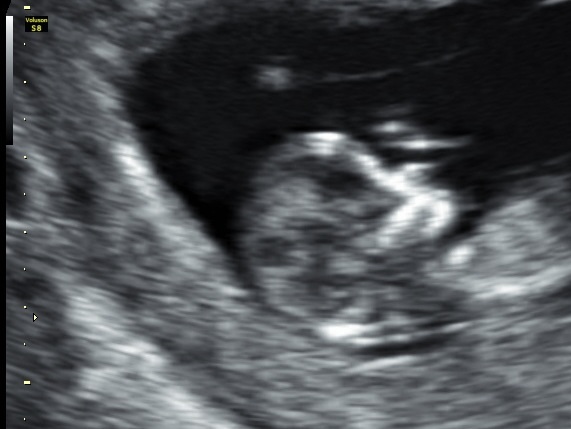

Hi everybody's here is a twelve week ultrasound pic, any guesses going by shape of the foreheads? Both are same baby!

The skull theory isn't too accurate at all. Do you have a nub shot of the lower extremities?

Maybe boy from skull pics?